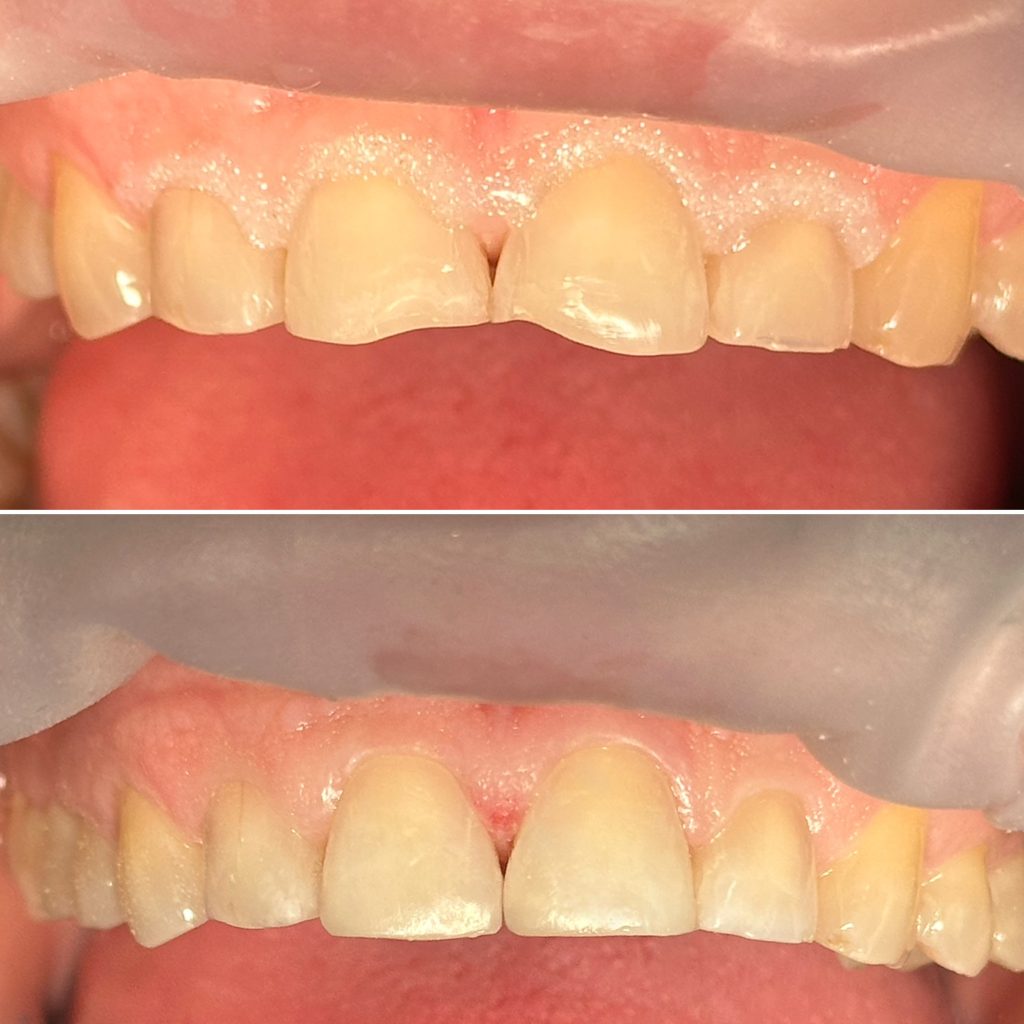

• Художественная реставрация фронтального и бокового участка зубов